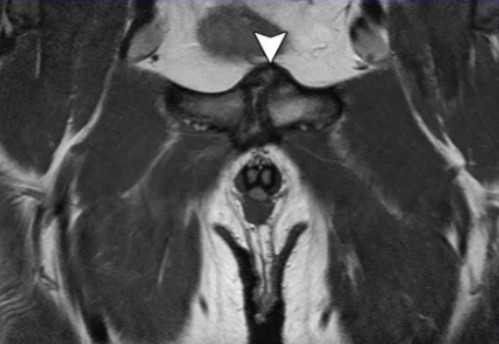

Импиджмент синдром на МР-фото

К механическому конфликту между бедренной головкой/шейкой и краем вертлужной впадины приводят одно- или двусторонние дефекты костей врожденного или приобретенного генеза. Видоизмененные компоненты сочленения вызывают дисфункцию конечности за счет соударения во время движения. Патологическое трение костей способствует разрастанию остеофитов на фоне постоянной травматизации вертлужной губы. Если своевременно не диагностировать заболевание и не начать лечение, последняя с течением времени разорвется., Хрящевая ткань сочленяющих костей будет разрушена. Подобный механический конфликт часто способствует формированию коксартроза и сопровождается прогрессирующим болевым синдромом.

МРТ тазобедренного сустава при феморо-ацетабулярном импинджмет-синдроме показывает возможные причины заболевания: